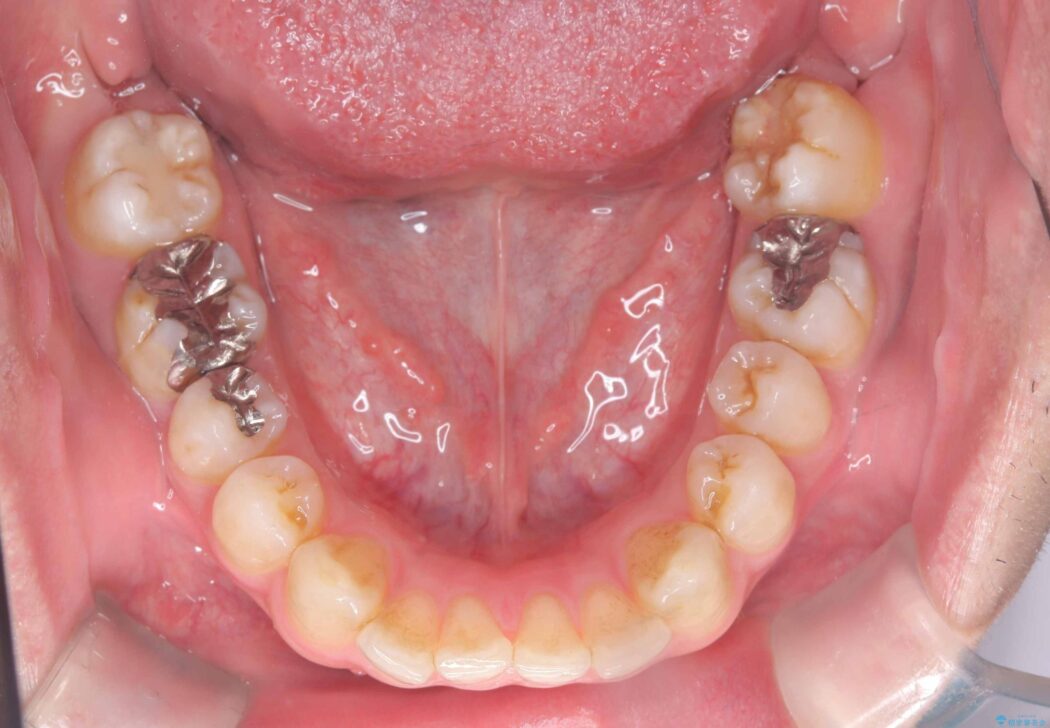

前歯の隙間とガタつきが気になるとご来院された患者様です。

正中離開・叢生のほかに、上下の奥歯が全く咬み合わないシザーズバイトの状態も認められました。